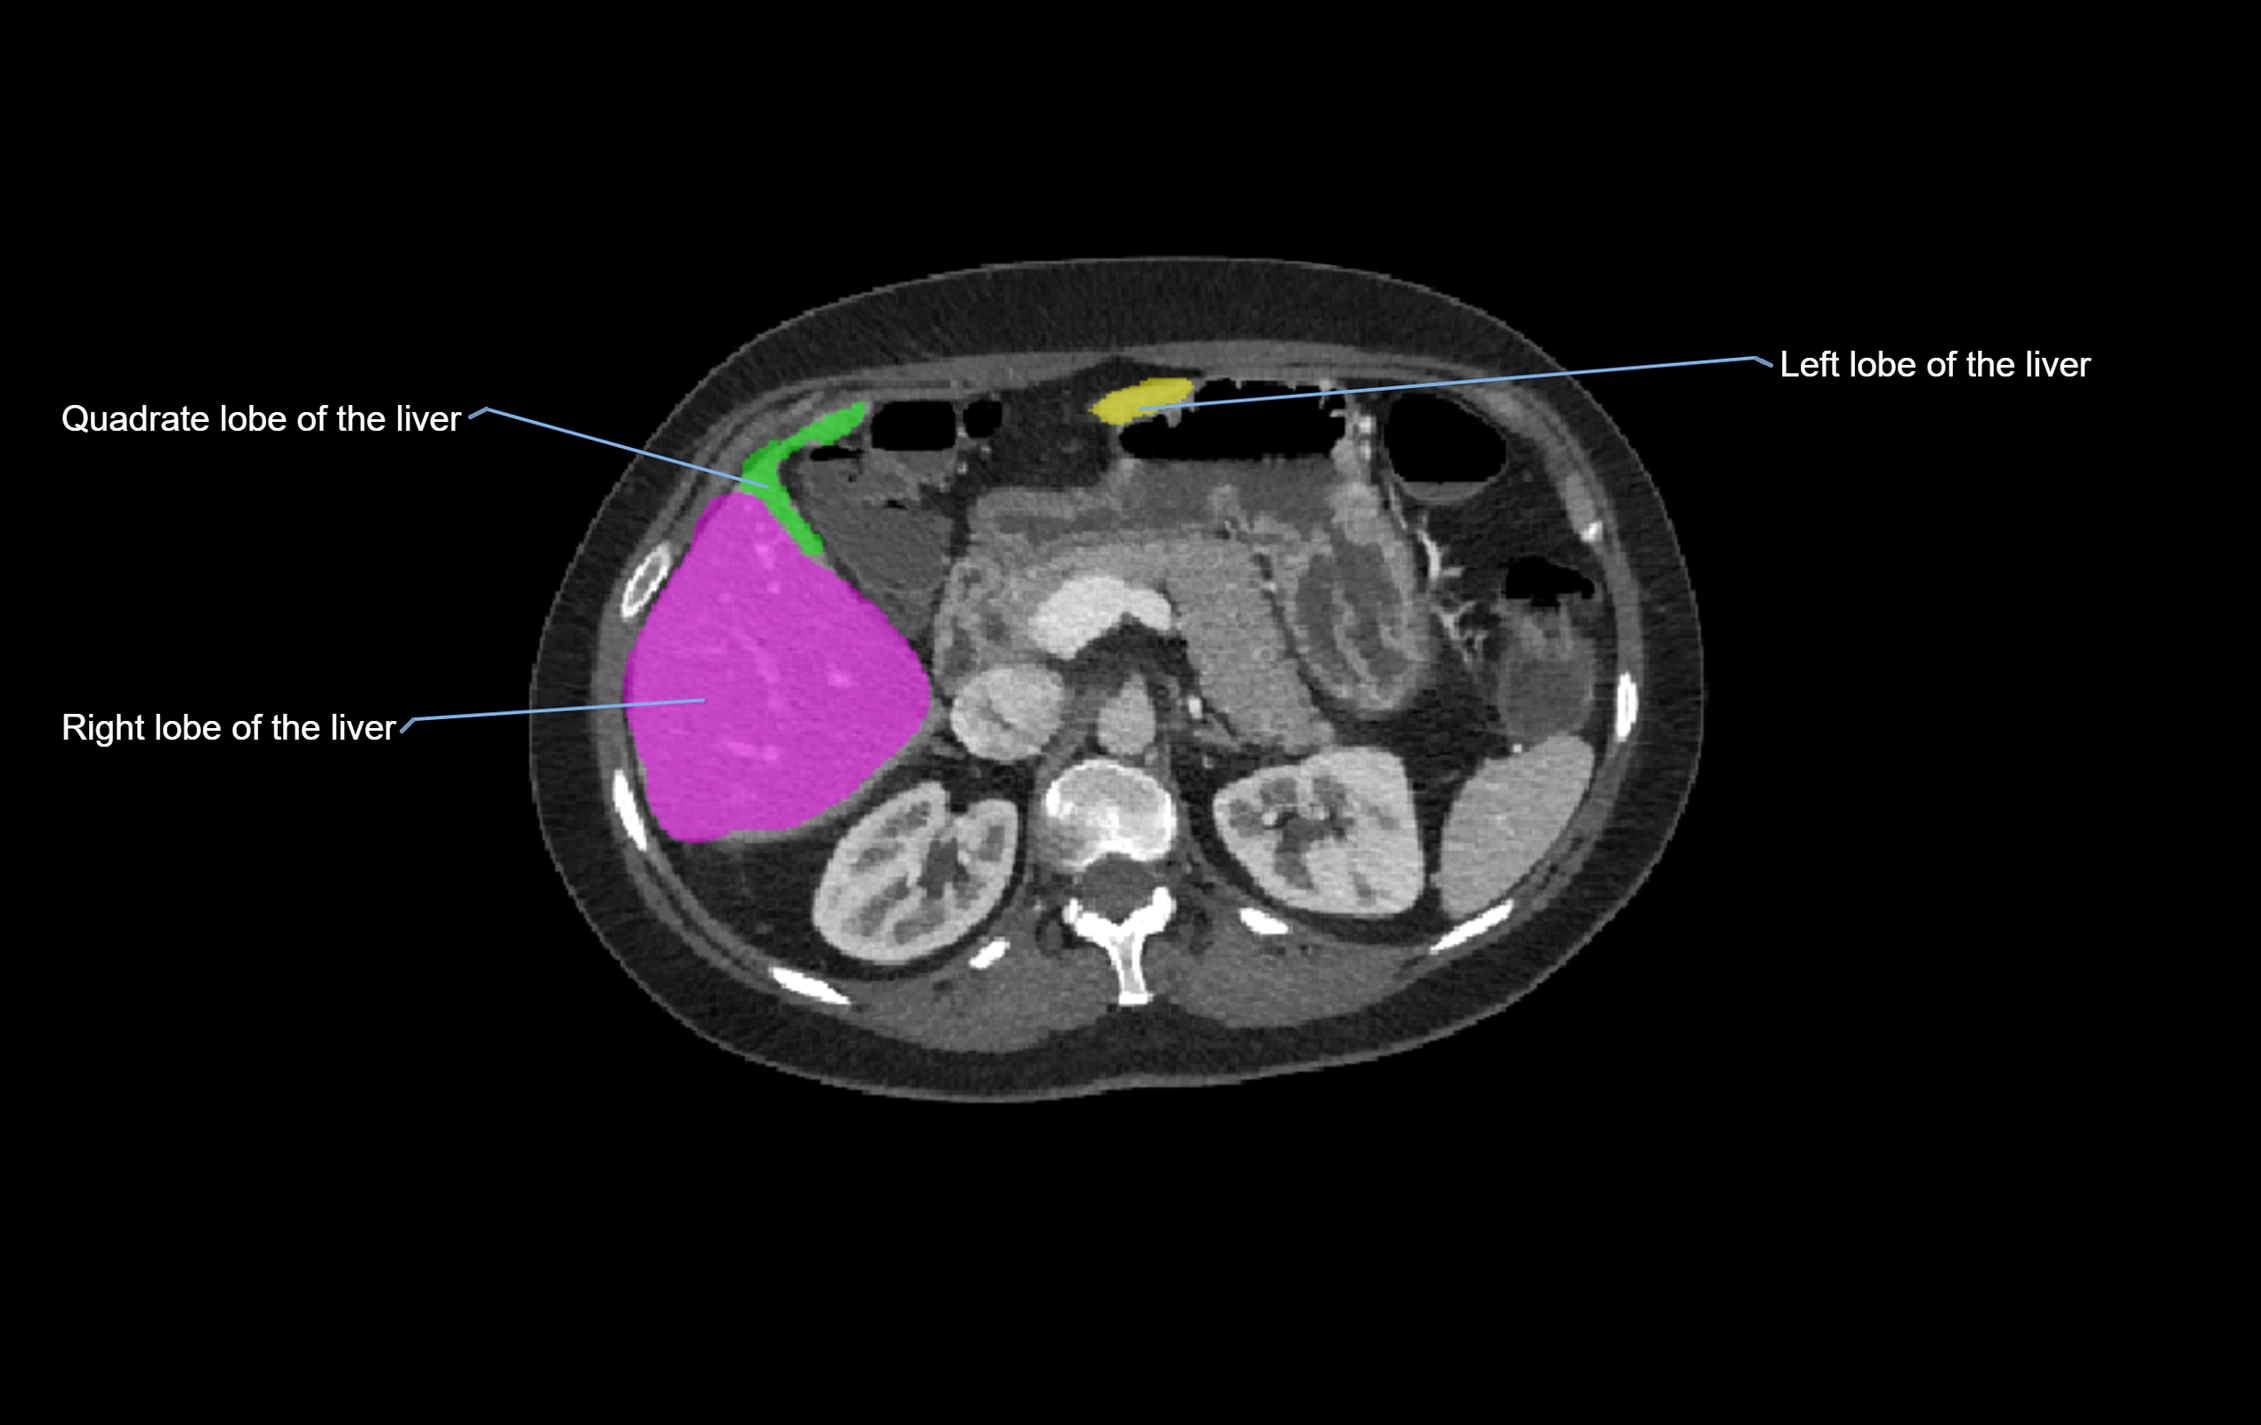

CT Image

image